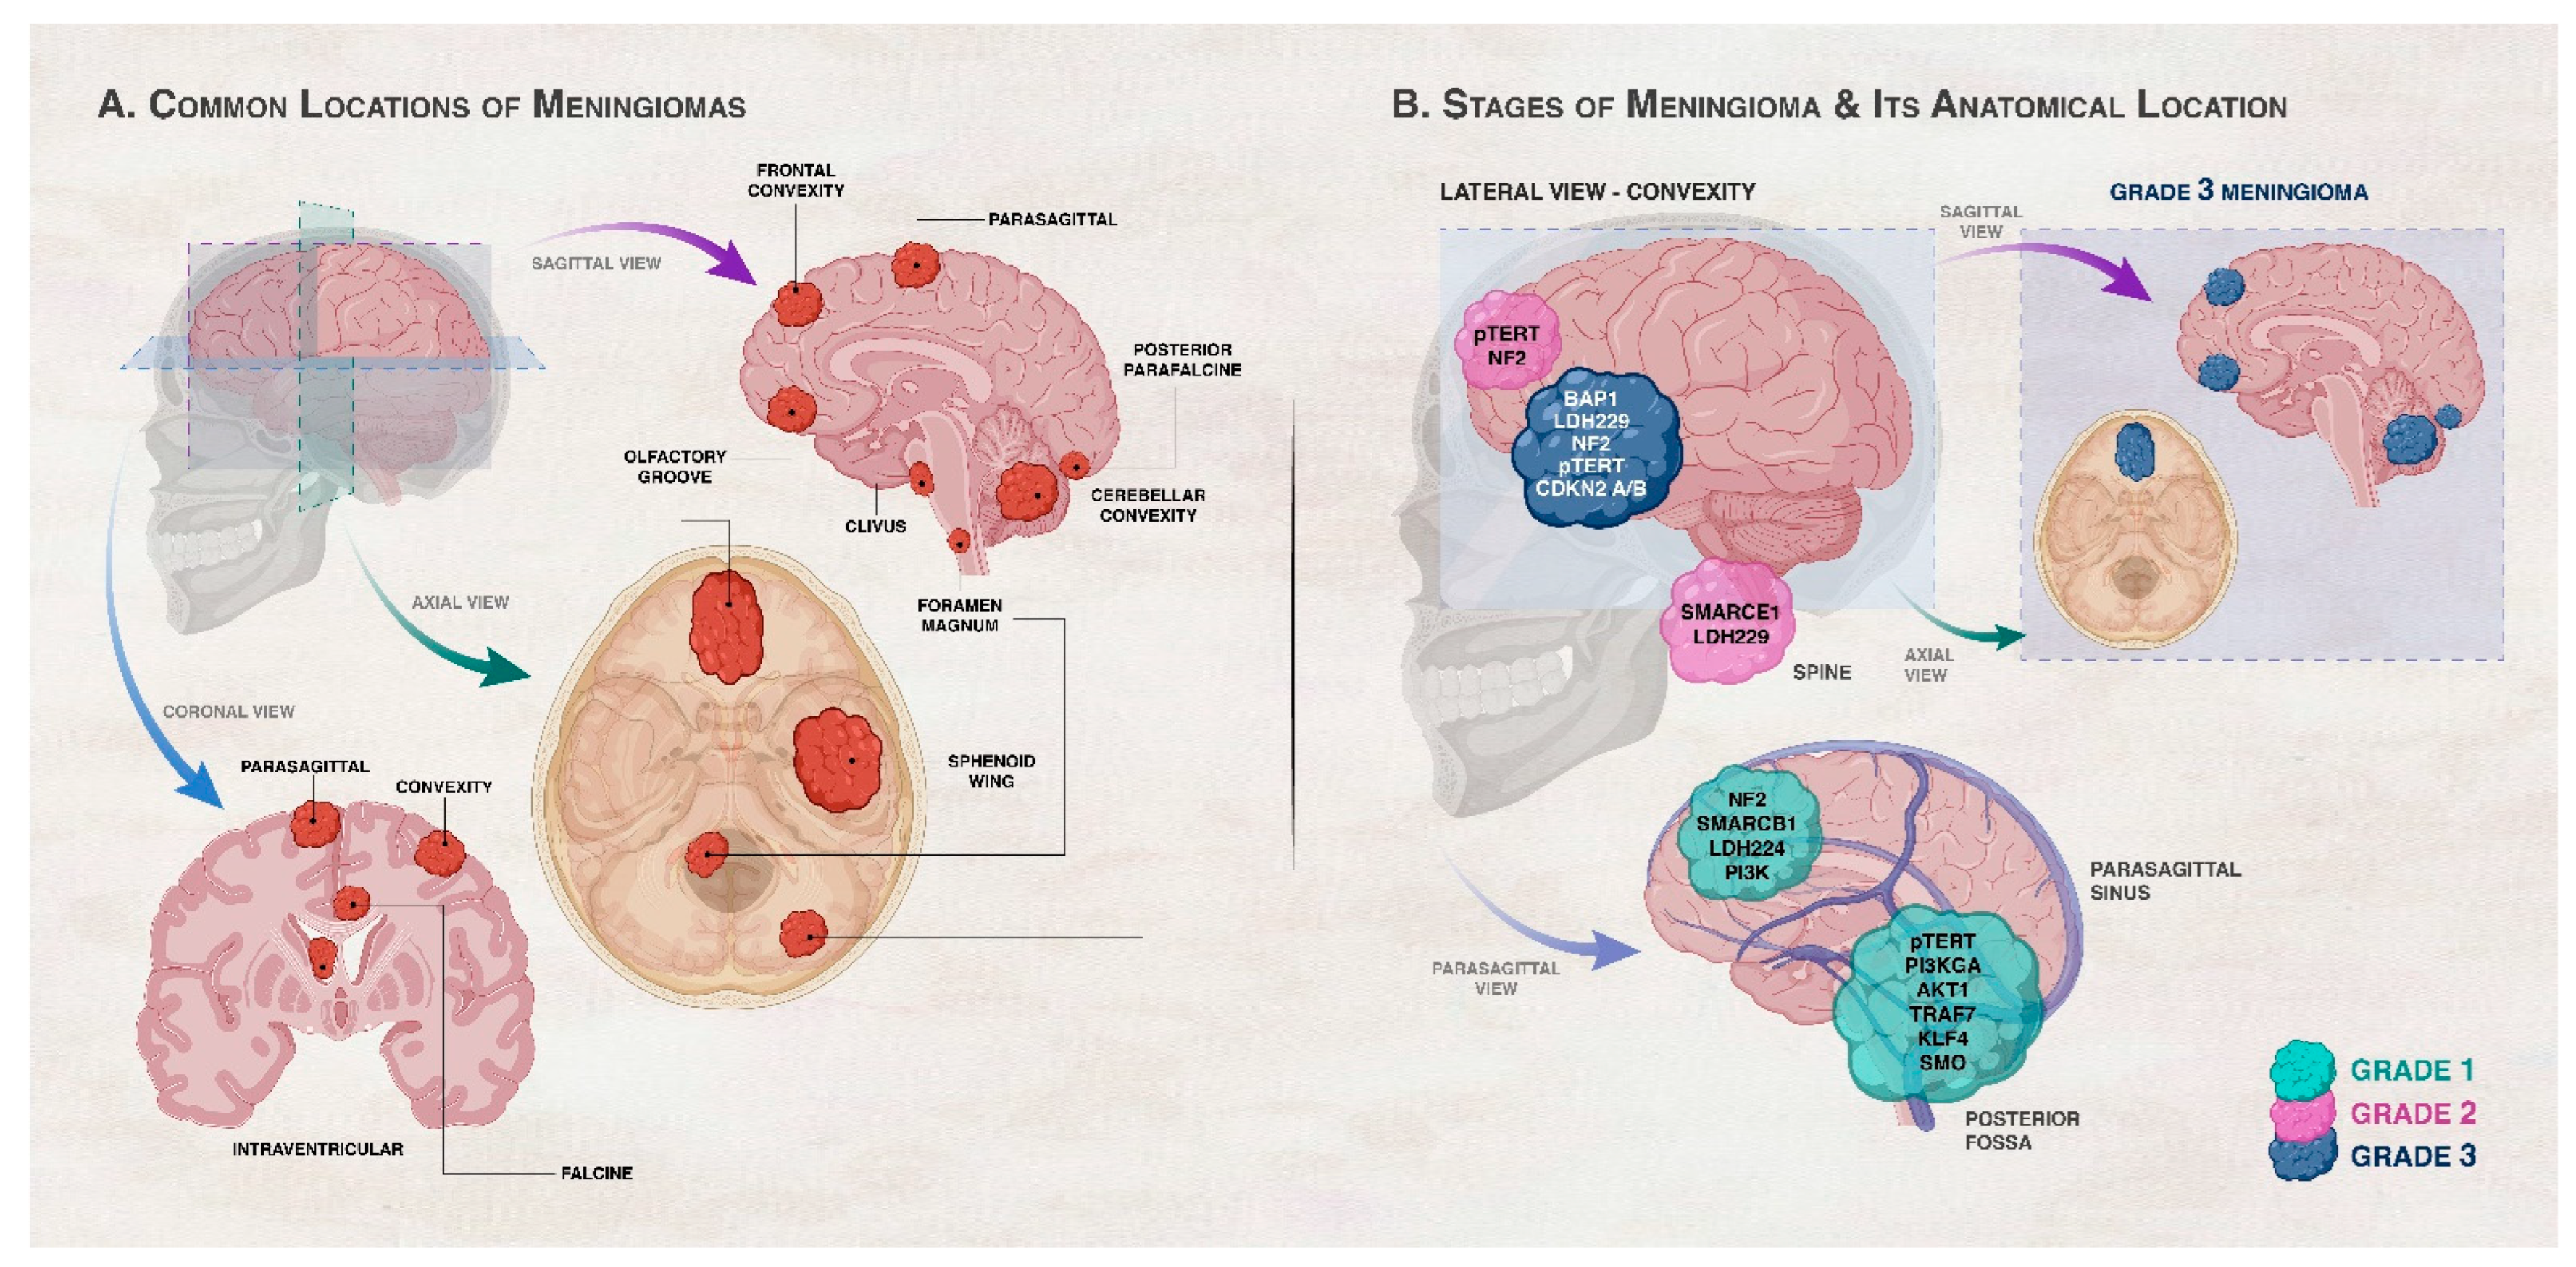

健康・医学 Meningiomas, Part II (Volume 170) i2 Meningiomas。Regression of Intracranial Meningiomas Following Treatment。Unveiling a Biomarker Signature of Meningioma: The Need for。Meningiomas, Part II (Volume 170) (Handbook of Clinical Neurology, Volume 170) ハードカバー – 2020/8/14英語版 Michael W. McDermott MD (編集)※中古品のため、使用できれば良いという方のみのご購入をお待ちしております。筋骨格系のキネシオロジー。※商品状態の少々の見落としはご理解下さい。骨形態計測ハンドブック/高橋栄明 著。※都合により発送方法を変更する場合があります。【美品・書き込みなし】精神薬理学エセンシャルズ/精神科治療薬の考え方と使い方。。The Evolving Classification of Meningiomas: Integration of。角に少々イタミあり。中古品のため、多少のスレ、イタミ等ありますが、書き込みなく、とても良好な状態です。気管支鏡テキスト 第3版。【美品】カパンジー機能解剖学(全3巻)。※値引交渉にはお答え致しません。※希少品の為、定価より高額の場合があります。常用カイロプラクティックマニュアル。【裁断済】スキル美容外科手術アトラス 眼瞼。【佐川急便/日本郵便から佐川急便/日本郵便及びその逆等】※ビニールにて梱包し発送致しますが、保管、輸送によるイタミ等はご容赦下さい。※コメント不要、即購入にてご注文お願いします。早わかり犬と猫の臨床 小動物臨床ハンドブックシリーズ 5

16153-9/asset/2fac6123-c7b5-4672-9706-47561c05fa86/main.assets/gr2_lrg.jpg)